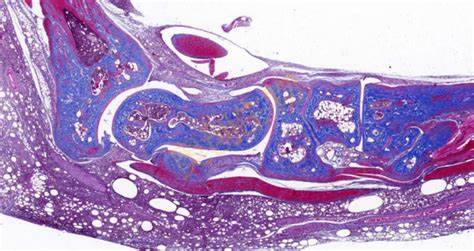

Masson染色是一种用于显示组织中纤维成分的特殊染色方法,主要用于区分胶原纤维和肌纤维,在病理学和组织学研究中有广泛的应用。**一、染色原理**1. 试剂作用 - **酸性复红**:它是一种酸性染料,能够将细胞质、肌纤维等染成红色。在染色过程中,酸性复红与肌纤维中的碱性蛋白结合,使肌纤维呈现出红

4008386992 立即咨询Masson染色是一种用于显示组织中纤维成分的特殊染色方法,主要用于区分胶原纤维和肌纤维,在病理学和组织学研究中有广泛的应用。

**四、结果观察与分析**

1. 细胞核

- 经过Weigert铁苏木精染液染色后,细胞核呈现黑色。可以观察细胞核的大小、形状、位置以及核内结构(如核仁),这有助于判断细胞的类型和状态。

2. 肌纤维

- 被酸性复红染色后呈红色,通过观察肌纤维的分布、走向和形态,可以了解肌肉组织的结构和功能。例如,在心肌组织中,心肌纤维呈分支状,相互连接成网状;在平滑肌组织中,肌纤维呈长梭形,排列较为规则。

3. 胶原纤维

- 被苯胺蓝染色后呈蓝色。可以观察胶原纤维在组织中的分布和含量,这对于研究组织的纤维化程度、创伤修复等过程具有重要意义。例如,在肝脏纤维化的组织中,会出现大量蓝色的胶原纤维增生。